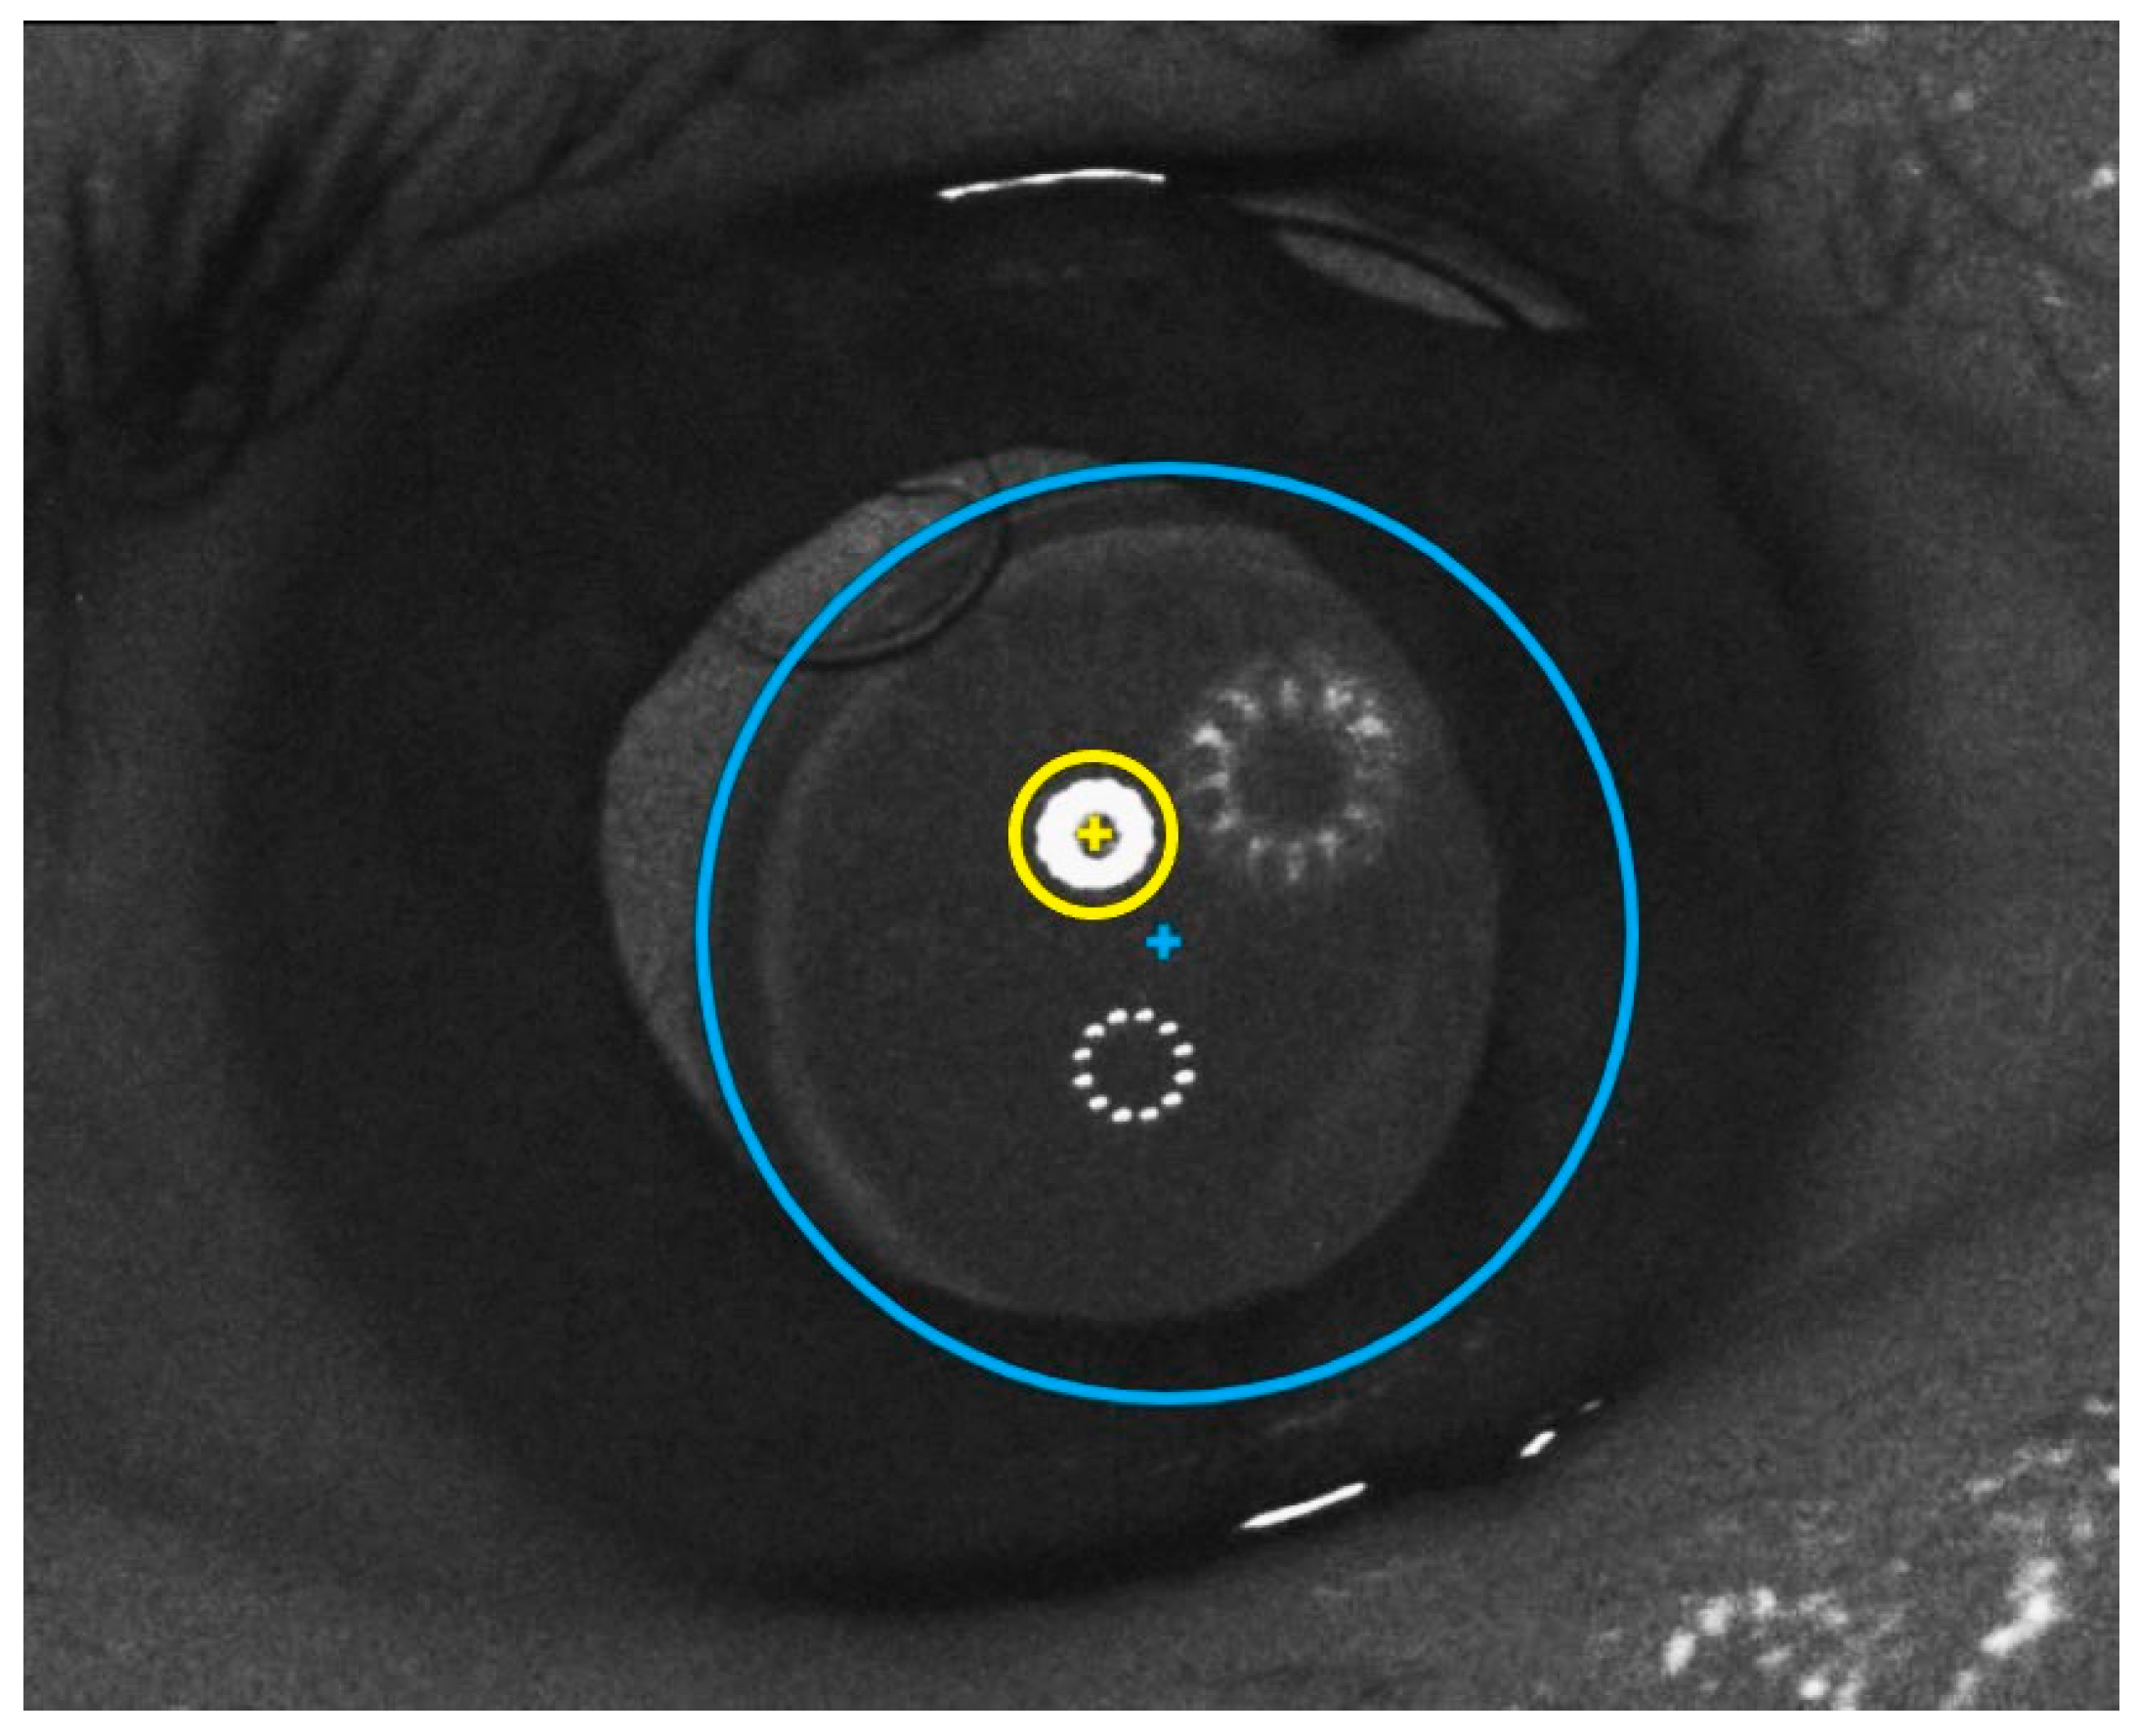

Secondly, the real IOL center decentration relative to the P1 position during the patient’s on-axis fixation was determined. This procedure followed the one that had been described above (Section 2.5): in the screenshot with the Purkinje image positions captured during the patient’s on-axis fixation, the IOL edge was interlaced with a circle (Figure 8). The center of this circle corresponds to the real IOL center. The real IOL center position (blue in Figure 8) was compared with the P1 center position (yellow in Figure 8) from the same image, and thus, the real value of the IOL decentration magnitude was obtained. This method is applicable only in eyes with sufficiently large pupils to see the IOL edge.

Figure 8. A photograph of a patient’s eye with circles representing interlaced structures in the custom-made software: P1 during on-axis fixation (yellow) and IOL edge (blue).